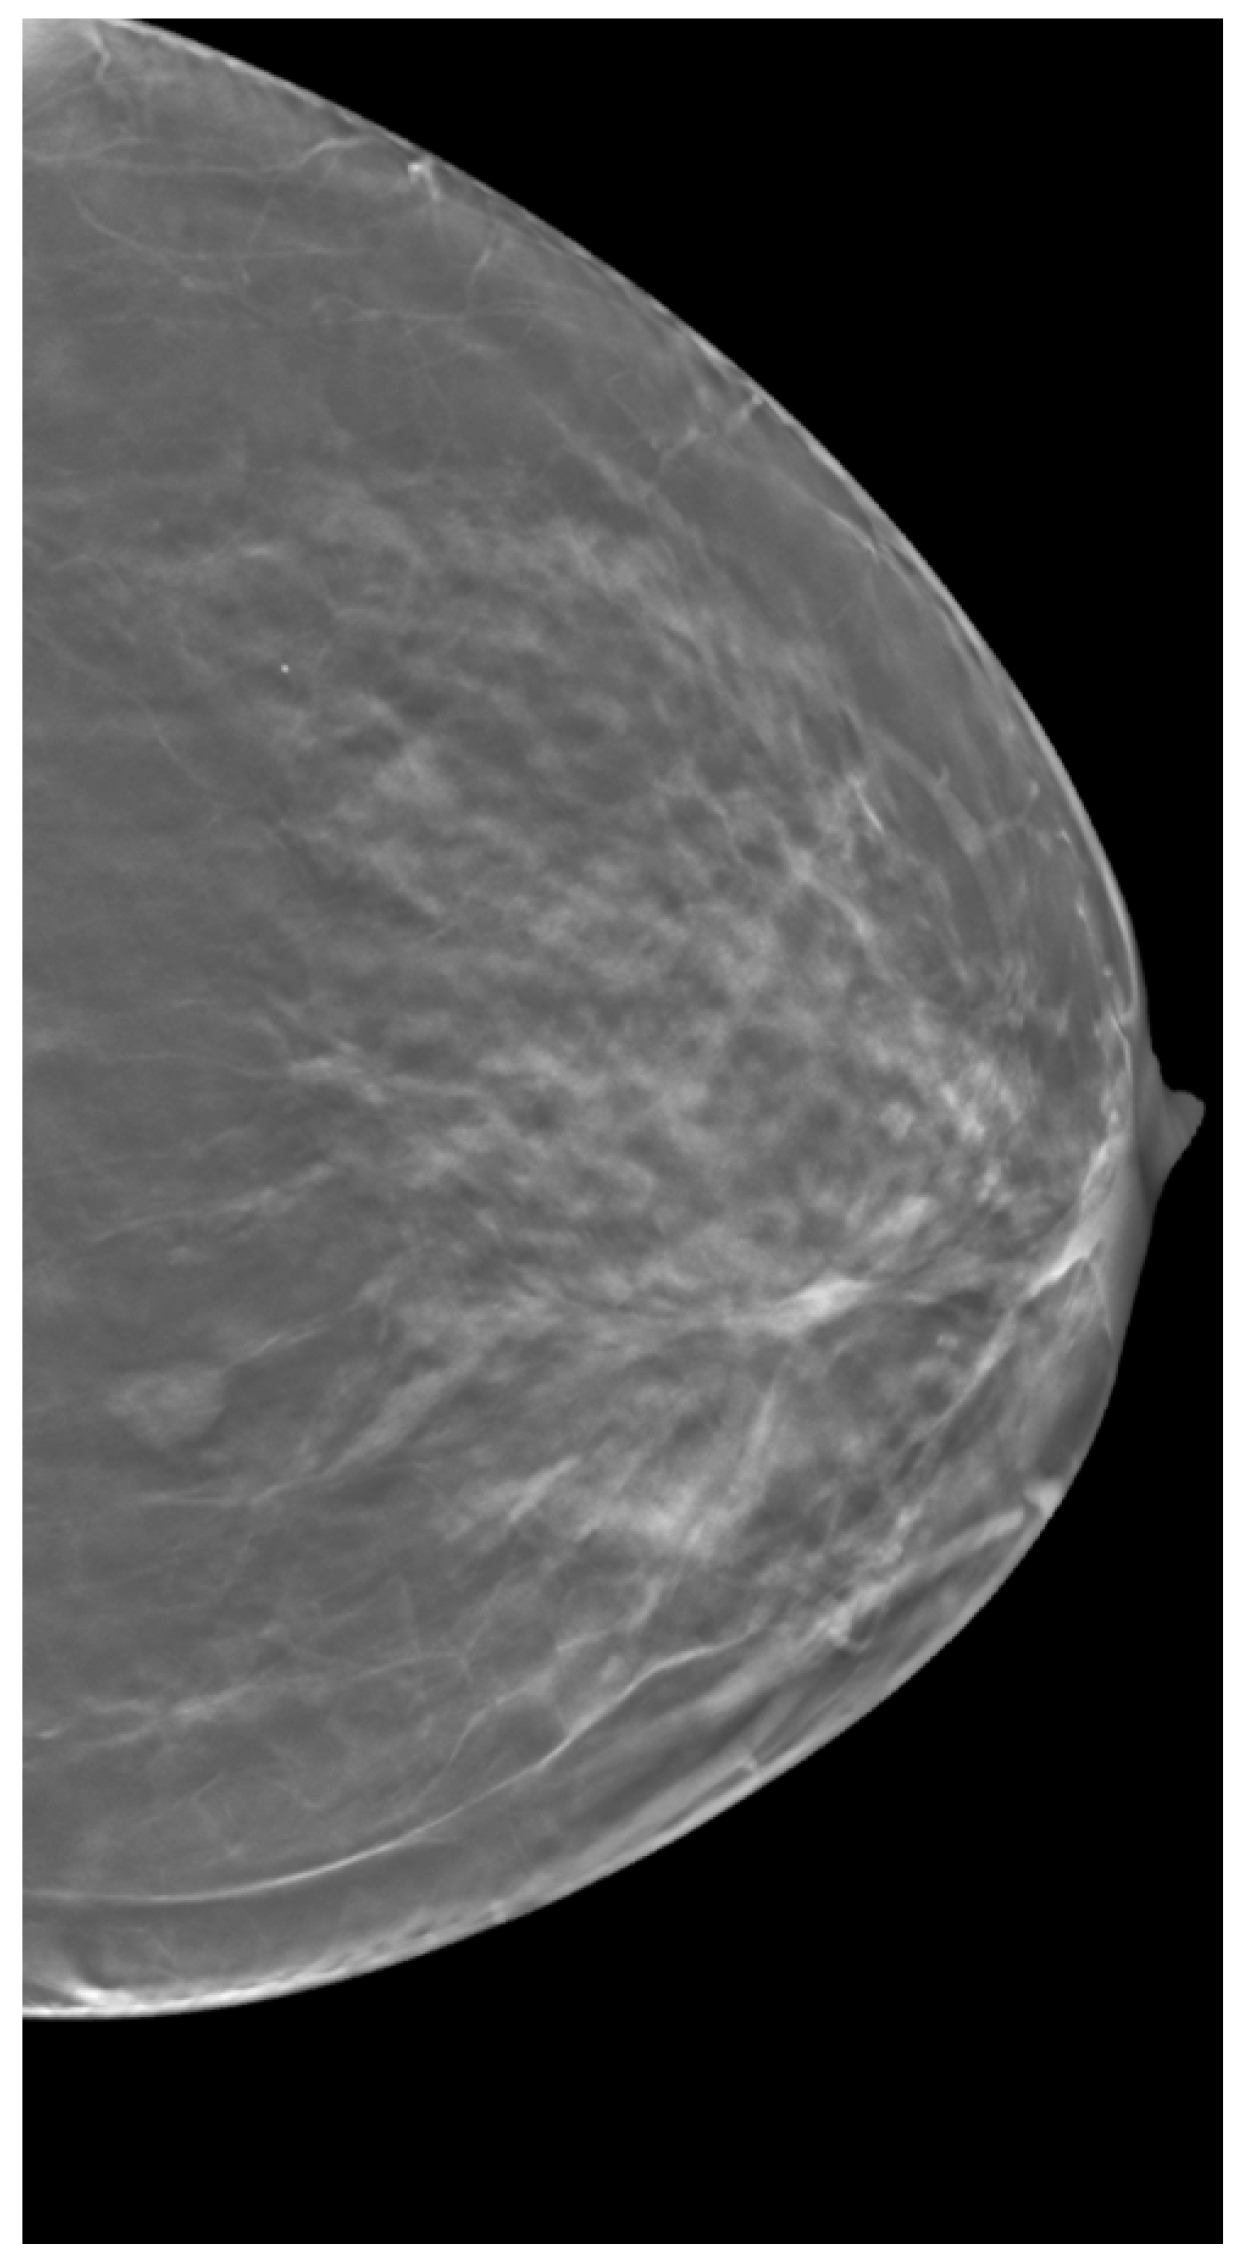

2.3. Clinical Data

3.3. Breast Density